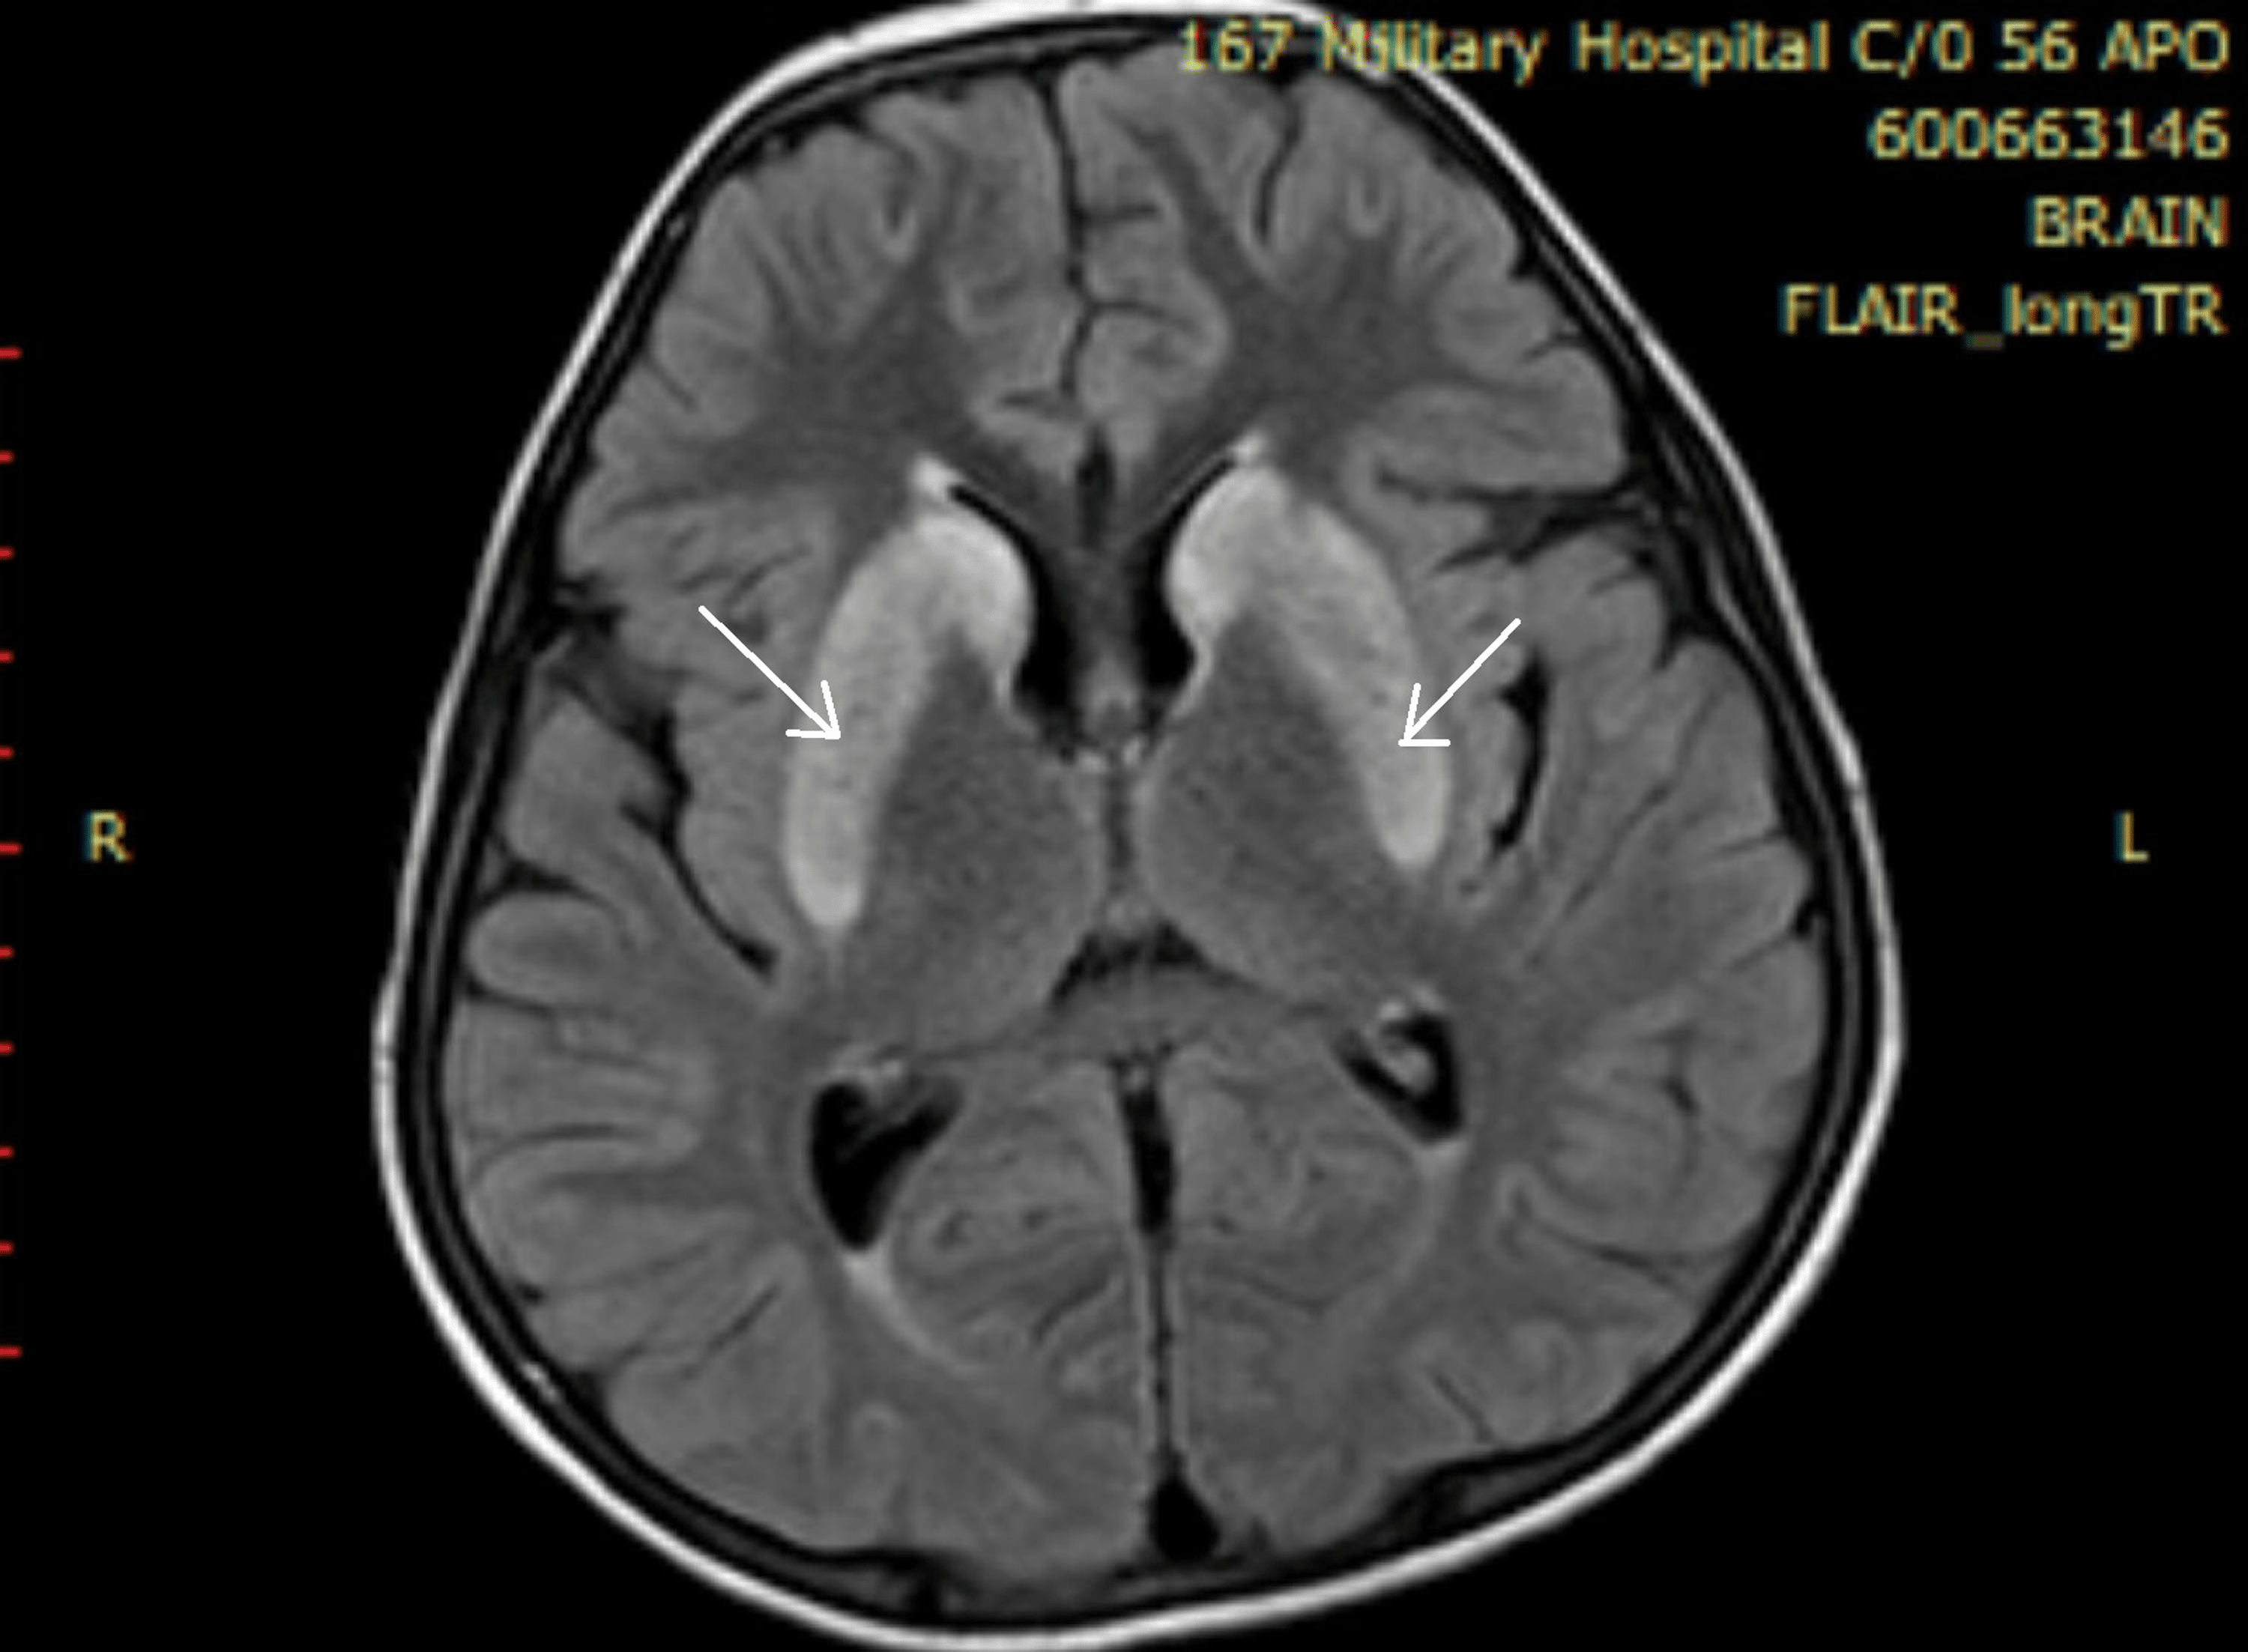

MRI brain in variant CJD axial FLAIR section at the level of the Basal Ganglia Hyperintensity Web t2 hyperintensity of the basal ganglia and thalami is generally present. Web basal ganglia and thalamus signal abnormalities occur in a wide variety of conditions. Web the basal ganglia are highly metabolically active and are symmetrically affected in. Web mri reveals t2w and flair hyperintensity involves the basal ganglia, and hyperintense lesions of the hemispheric cerebral white. Web the. Basal Ganglia Hyperintensity.